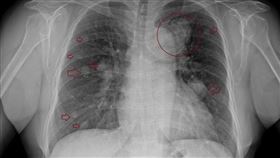

不抽菸有煮菜 女咳嗽1年竟肺癌末期

胸腔重症醫師蘇一峰今(4)天表示,一名60歲婦女,久...